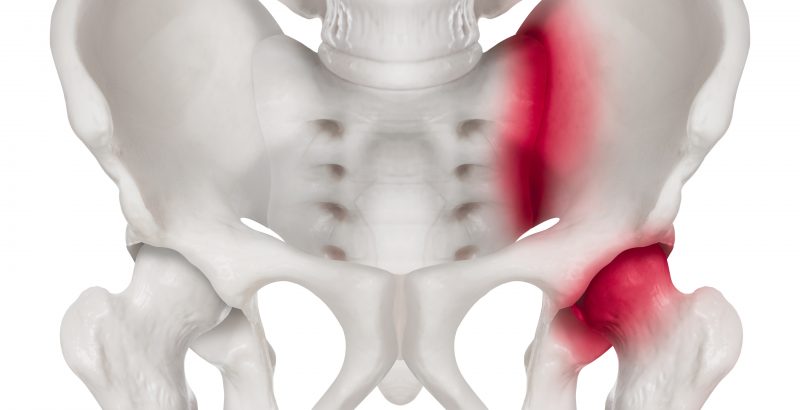

O que é a neuroestimulação? A neuroestimulação é uma técnica médica que utiliza impulsos elétricos de baixa intensidade para modular a atividade do sistema nervoso central e periférico. Ao interferir com os sinais de dor que vão da periferia do nosso corpo para o cérebro, este tratamento oferece um alívio significativo e duradouro para muitas […]